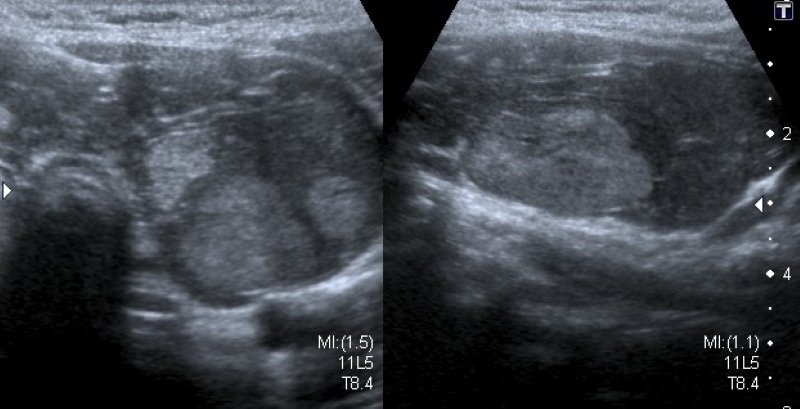

Calcificaciones

Focos ecogénicos que pueden clasificarse según su tamaño en microcalcificaciones (Fig. 15) y macrocalcificaciones (Fig. 16). Las primeras miden menos de 1 mm y no presentan sombra acústica posterior, a diferencia de las macrocalcificaciones que son mayores de 1 mm con sombra acústica posterior.

Las microcalcificaciones presentan un alto riesgo de malignidad. De hecho, algunos autores las consideran por sí solas un predictor de malignidad20, y otros sostienen que la presencia de microcalcificaciones sumado al aumento de la vascularización central y una imagen ganglionar patológica son suficientes para indicar una punción aspiración con aguja fina23.

El artefacto en cola de cometa (Fig. 17) es producido por la reverberación en los quistes coloides, que pueden confundir con microcalcificaciones. A diferencia de estas últimas, el artefacto en cola de cometa se visualiza como una línea ecogénica brillante con un triángulo o líneas ecogénicas posteriores, y se suele asociar a benignidad2.